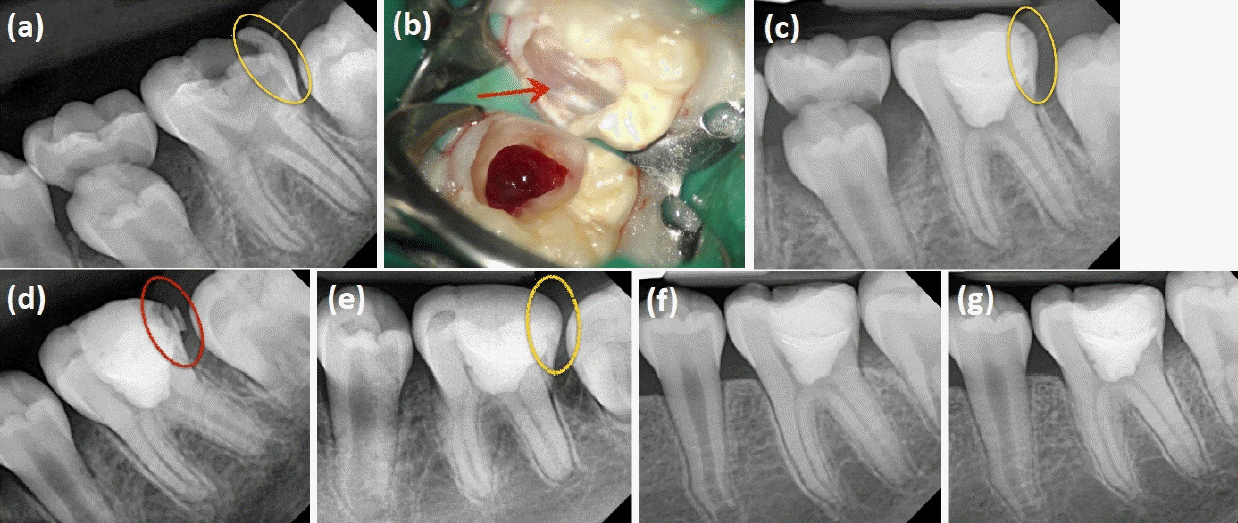

Figure 4.

Case of partial pulpotomy on the left mandibular first molar in a 10-year-old female patient. (a) The tooth was minimally erupted, with the occlusal surface nearly at the same level as the posterior gingiva. The distal enamel was thinly remaining (yellow circle). (b) After caries removal, only a thin layer of distal enamel remained, making the underlying gingival tissue visible through it (red arrow). (c) The partial pulpotomy was completed while preserving the thin enamel layer. (d) After four months, the patient returned with a fractured distal tooth structure, which was restored with resin. (e) At 10 months, the resin restoration remained intact without any issues. (f) 16-month and (g) 22-month follow-ups showed continued stability. Nearly two years after treatment, the permanent dentition had fully erupted, and tooth #36, along with adjacent teeth, had properly erupted. The patient is now scheduled to replace the resin restoration with an indirect restoration.